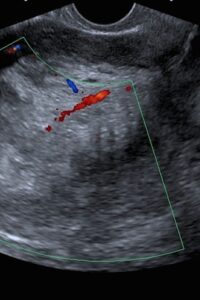

Cancer of the ovary and the fallopian tube- this is one of the most dreaded cancers of the female genital organs, and this because it is asymptomatic until a late stage. Often it is difficult to determine whether the cancer originated in the in the tube or ovary due to the close proximity of the two, and because the same histological type of cancers can occur in both.

Hence we recommend a yearly pelvic scan to detect any tumors or cysts of the ovary or fallopian tubes. In addition, the ovarian cancer spreads rapidly to neighboring organs, because of the rich blood supply to the ovary.

Hence an early diagnosis ensures an optimal outcome.